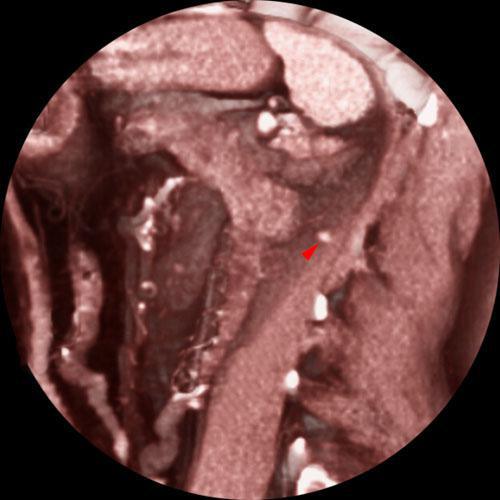

Nefrectomía parcial. Tumorectomia